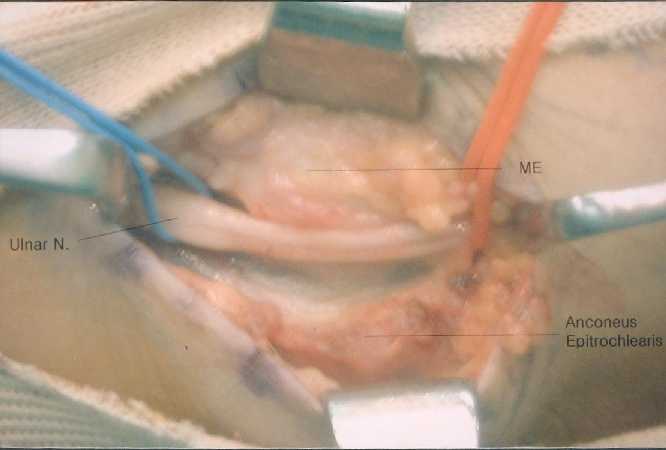

crossed the ulnar nerve from olecranon to medial epicondyle, which was found to be the anconeus epitrochlearis muscle. The ulnar nerve was compressed by the aberrant muscle and a fusiform thickening and induration of the nerve trunk were observed just proximal to the muscle. The muscle was tight in flexion and significantly compressed the ulnar nerve. The ulnar nerve was strained proximal to the muscle bulk at elbow flexion beyond 90. The aberrant muscle was split longitudinally and flexor retinaculum as well. Splitting of the muscle revealed the aberrant muscle was hypertrophied as thick as 5 millimeter in depth and compressed the nerve during elbow flexion. It disclosed narrowed area of ulnar nerve 10mm under the muscle

(Figure 2)

No epineural or perineural neurolysis was performed.